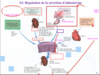

ils filtrent continuellement le sang et plus particulièrement le plasma (150 à 180 L/jour) et n’excrètent qu’environ 1% de ce volume (1,5 à 1,8 L/jour) sous forme d’urine

rôle important dans la régulation du volume et de la composition chimique du sang (équilibre hydroélectrolytique, pH)

- excrétion dans l’urine des déchets métaboliques, toxines, substances chimiques, etc.

- mais réabsorption de substances indispensables à l’équilibre du milieu intérieur (régulation de l’homéostasie)